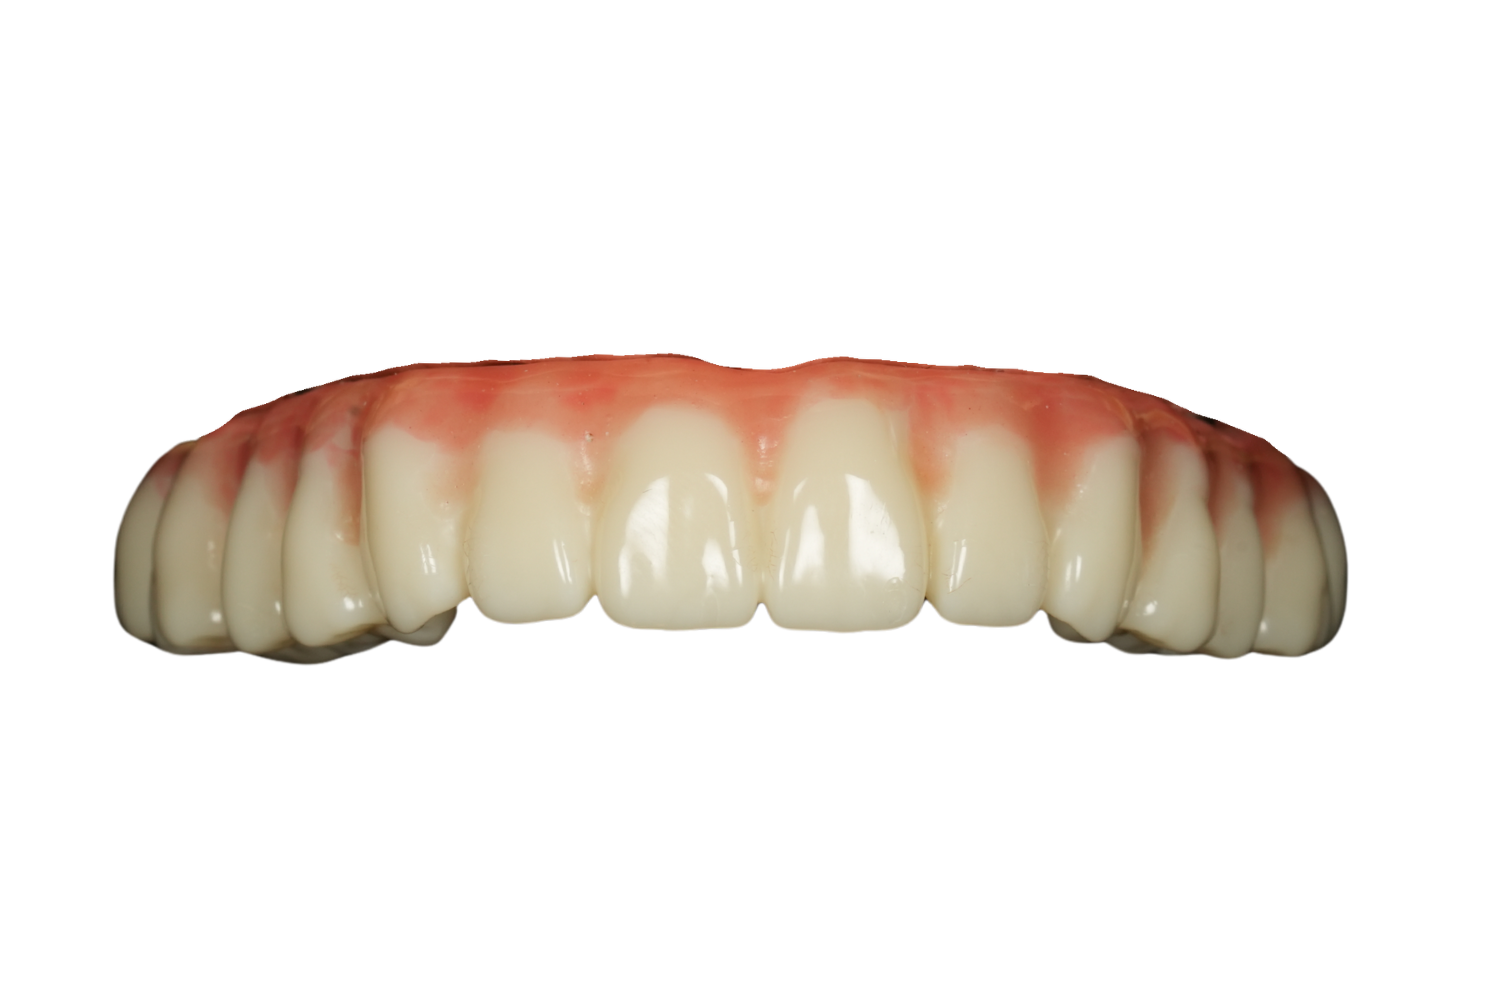

案例1. 上顎+下顎All on X

Before

After